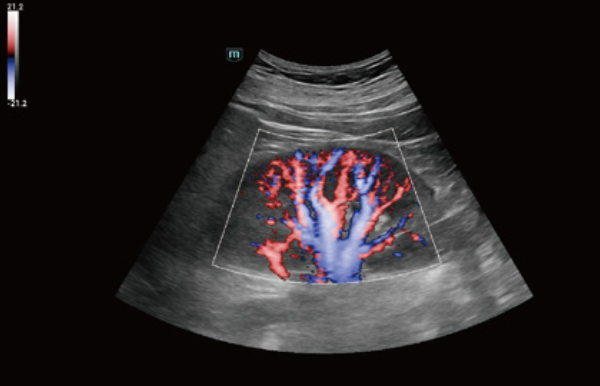

Uitgebreide?oplossingen voor beeldvorming aangestuurd door ZST?+

Het ZST+?platform is een buitengewone innovatie en revolutie in de wereld van echografie. Het transformeert echografiegegevens van conventionele bundelvorming naar kanaalgegevensverwerking. Het overwint de traditionele afweging tussen ruimtelijke resolutie, temporele resolutie en weefseluniformiteit, en levert een uitzonderlijke beeldkwaliteit voor oneindige beeldvormingsoplossingen met non-stop verbeteringen.